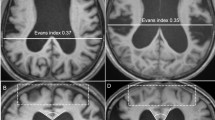

Fifty (20 female/30 male) consecutive patients with INPH who underwent shunt surgery at Tohoku University Hospital between August 2006 and October 2010 and 10 healthy control (HC) subjects (mean age: 65.1 ± 3.6 years, 5 females and 5 males) were enrolled in this study. The patients were diagnosed with probable INPH by board-certified neurologists based on the diagnostic criteria established according to the Japanese Clinical Guidelines for INPH [16]. The criteria for probable INPH are as follows: (1) >60 years of age; (2) gait disturbance, dementia, and/or urinary incontinence; (3) ventricular dilatation (Evans index >0.3) with a narrow cerebrospinal fluid (CSF) space in the superior convexity; (4) CSF pressure <200 mm H2O with normal CSF cell counts and protein levels; (5) the absence of other diseases that may account for such symptoms; (6) the lack of a previous history of illness that may cause ventricular dilatation; and (7) a positive CSF tap test.

The comparison of FA maps between baseline and 1 year after shunt placement in the SR group are shown in Fig. 5a and Table 3C. The FA values were significantly decreased in the left corona radiata. In addition, the result of the back-projection revealed the precise registration of each FA map. The anatomical ROI of the left corona radiata of each SR or SNR patient was placed using colour-coded FA map and referring to the result of the TBSS analysis (Fig. 5b). The anatomical ROI analysis showed that the mean FA value of the regions in the left corona radiata was significantly decreased after shunt placement only in the SR group (Table 2A). There were no other regions in which the FA values were significantly increased after shunt placement in the SR group. In the comparison of the FA map between baseline and 1 year after shunt placement in the SNR group, there were no regions in which the FA values were significantly altered. In the comparison of MD maps between baseline and 1 year after shunt placement, there were no regions in which the MD values were significantly altered in either the SR or the SNR groups.

White matter regions in which FA values significantly changed after shunt placement. a Demonstrates the areas with significantly decreased FA values after shunt placement in the shunt-responsive INPH patients using colours ranging from light-blue to pink (p < 0.05, corrected for multiple comparisons by using TFCE). b Shows the position of the anatomical ROI. On colour-coded FA map, red, green, and blue represent the direction of fibres (red, right-left; green, anterior-posterior; blue, superior-inferior). The ROI was placed on the blue regions in the left radiata on the axial slice that included the genu of the corpus callosum. A anterior, L left, P posterior

FA values in the corpus callosum and in the SWM of the convexity and occipital cortex were significantly lower in SR than in HC, whereas MD values in the periventricular and peri-Sylvian white matter were significantly higher. These findings were frequently reported in the previous DTI studies [10, 15]. The white matter regions in which FA values were decreased after shunt placement were distributed in the left corona radiata. These regions were located between the lateral ventricle and the Sylvian fissure, and therefore may have been severely compressed. Recent studies reported that the FA values of the CST near the lateral ventricles in INPH were higher compared with those in healthy controls, although this result was not confirmed in the present study [10, 11]. Hattori et al. detected the increase of axial eigenvalues and unaltered radial eigenvalues in the CST and suggested that mechanical pressure from ventricular dilatation could enhance directional water diffusivity parallel to the axon in the CST in INPH [11]. In addition, we speculated that dilatation of the Sylvian fissures could play a role of counterfort against mechanical pressure from the ventricular dilatation in INPH. It is considered that the release of compression to the corona radiata including the CST and projection fibre to the medial frontal cortex, which is thought to play a role in planning or programming voluntary movements including gait, is associated with clinical improvement after shunt placement [9, 33, 34].